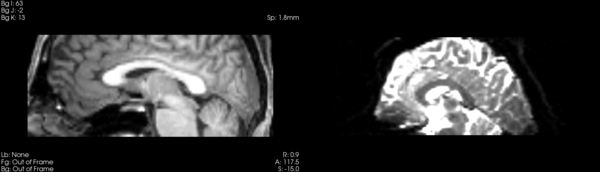

Affine

- 53-t2 -> 31-t1 = aff1

- aff1 -> 53-t2 = aff2

The image shows these side by side. The are nearly the same except for the loss of fine detail.